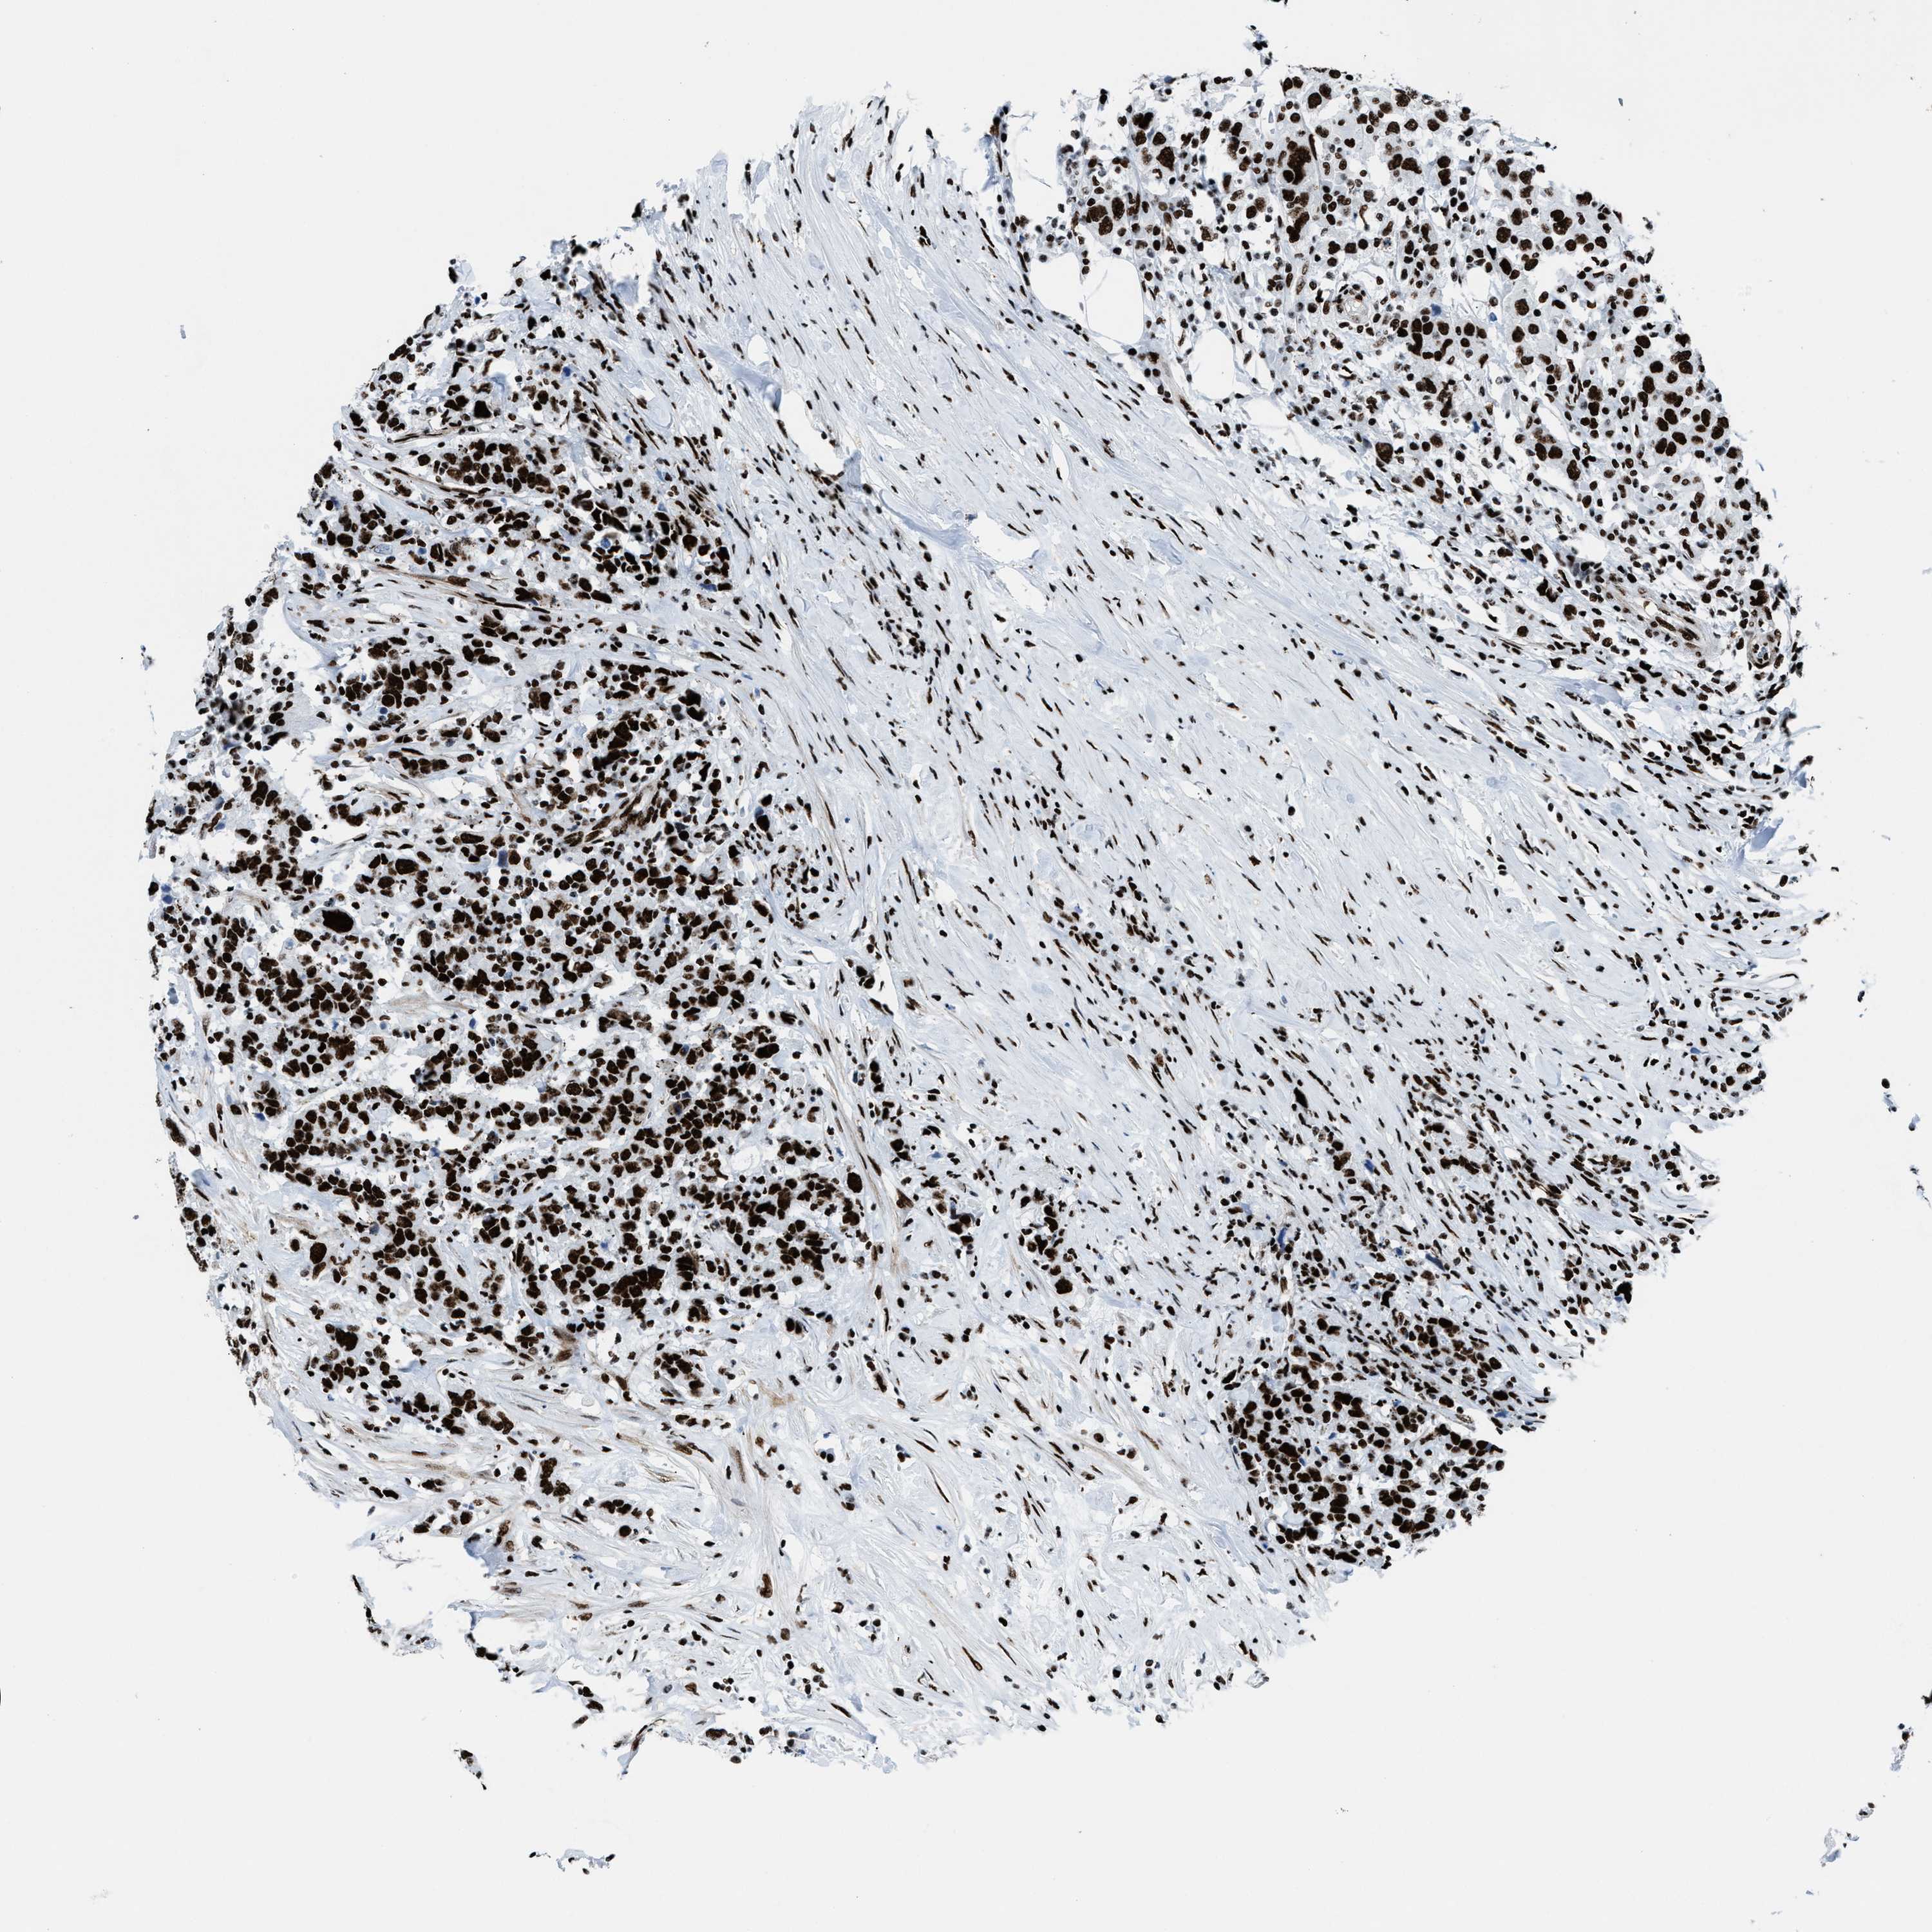

UROTHELIAL CANCER - Protein expressioni

A mouse-over function shows sample information and annotation data. Click on an image to view it in a full screen mode. Samples can be filtered based on level of antibody staining by selecting one or several of the following categories: high, medium, low and not detected. The assay and annotation is described here.

Antibody stainingi

Antibody staining in the annotated cell types in the current human tissue is reported as not detected, low, medium, or high, based on conventional immunohistochemistry profiling in selected tissues. This score is based on the combination of the staining intensity and fraction of stained cells.

Each image is clickable and will lead to virtual microscopy that enables deeper exploration of all samples and also displays staining intensity scores, fraction scores and subcellular localization as well as patient and tissue information for each sample.

Antibody HPA054094

Antibody HPA054559

Antibody CAB022069

Staining

High

Medium

Low

Not detected

Intensity

Strong

Moderate

Weak

Negative

Quantity

>75%

75%-25%

<25%

None

Location

Nuclear

Cytoplasmic/membranous

Cytoplasmic/membranous,nuclear

Urothelial carcinoma, High grade

Urothelial carcinoma, NOS

Urothelial carcinoma, Low grade